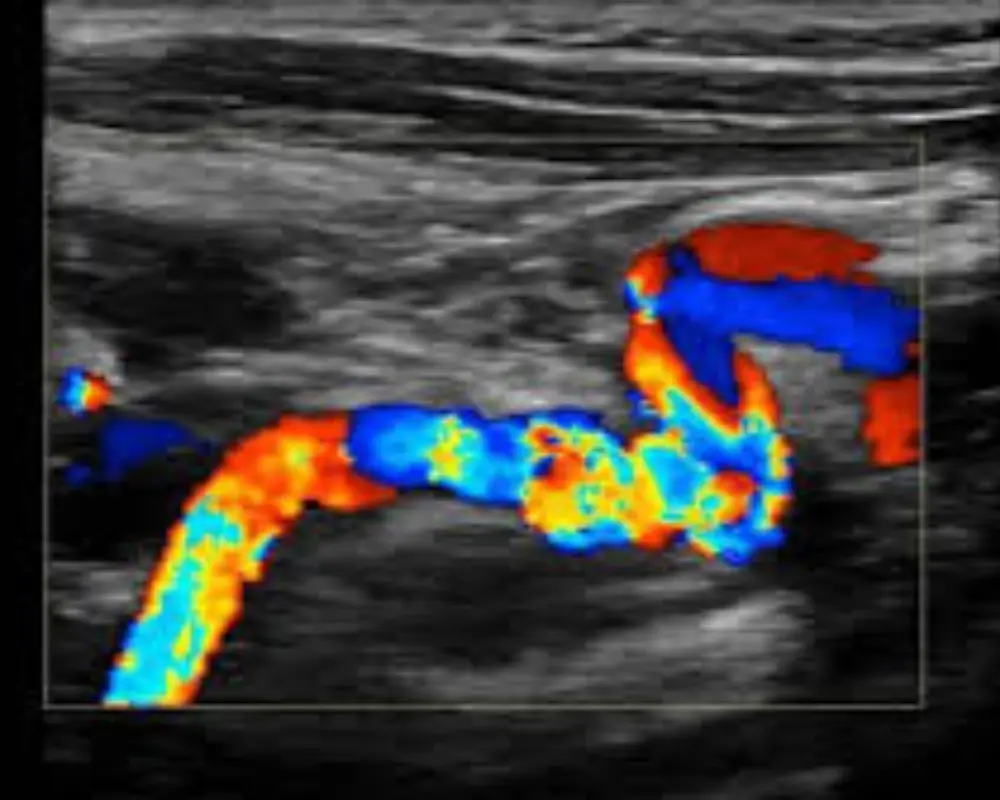

Vascular Ultrasound

Vascular ultrasound evaluates blood flow in arteries and veins, helping detect blockages, clots, and circulation issues with precise, non-invasive diagnostic imaging technology.